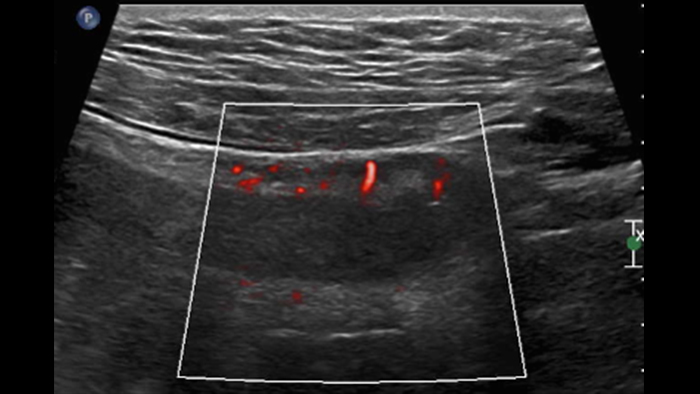

Ces images précises des lésions des couches pariétales forment la base de l’interprétation des changements induits par l’inflammation des parois intestinales et par conséquent de la différenciation entre la maladie de Crohn et la rectocolite hémorragique. L’exploration avec la technologie MFI (MicroFlow Imaging) constitue la deuxième étape. Il s’agit de reconnaître l’aspect de l’hypervascularisation induite par des épisodes inflammatoires actifs. La paroi intestinale normale semble comporter peu de microvaisseaux détectables, uniquement à l’interface de la muqueuse et de la sous-muqueuse, et dans le tissu adipeux mésentérique adjacent. Inversement, la paroi inflammatoire présente de nombreux microvaisseaux. La distinction entre les images d’artefacts de mouvement et les microvaisseaux circulants est alors un point essentiel nécessitant un ajustement parfait des paramètres de détection des micro-flux (voir les boucles, diapositive 8). La comparaison des 4 images suivantes de la maladie de Crohn met en évidence des différences claires qui devraient être interprétées comme étant représentatives des différents états inflammatoires. L’image 1 ne comporte aucun vaisseau visible, ce qui correspond probablement à une absence d’activité. L’image 2 présente quelques vaisseaux ; nous pouvons en conclure que cela correspond à une activité modérée. L’image 3 comporte un plus grand nombre de vaisseaux, signe probable d’une activité intense. L’image 4 présente encore plus de vaisseaux de type pulsatile, ce qui évoque probablement une activité très intense.

Les images sont absolument différentes selon l’état inflammatoire. C’est une question de densité, de pulsatilité, mais également de localisation des vaisseaux. C’est l’avantage de la superposition des images de micro-flux à celles des couches pariétales obtenues par échographie haute résolution. Sur les images suivantes, accompagnées des clichés d’IRM correspondants, il semble que dans le premier cas, à savoir une maladie de Crohn d’apparition récente, les vaisseaux soient localisés à la surface de la paroi intestinale, probablement au niveau de la muqueuse. En revanche, dans les autres cas de maladie plus avancée, ils sont également plus visibles à l’intérieur de la sous-muqueuse et dans le tissu adipeux adjacent.

Est-ce si simple ? Probablement pas car 2 questions importantes restent en suspens : Les paramètres d’acquisition MFI doivent donc être adaptés à la réduction des artefacts sans masquer le micro-flux des vaisseaux. Les deux images suivantes de la même paroi intestinale sont obtenues avec des paramètres différents en termes de sensibilité du micro-flux et de détection de la vélocité. Après ajustement des paramètres, la deuxième image permet apparemment d’effacer les artefacts de mouvement (petites taches) tout en laissant les microvaisseaux pariétaux (images linéaires) clairement visibles. Il semble que cet ajustement ne soit pas toujours facile à obtenir pour valider la signification des images de micro-circulation de flux, et donc la densité des microvaisseaux, qui constitue l’information principale pour détecter une inflammation aiguë.